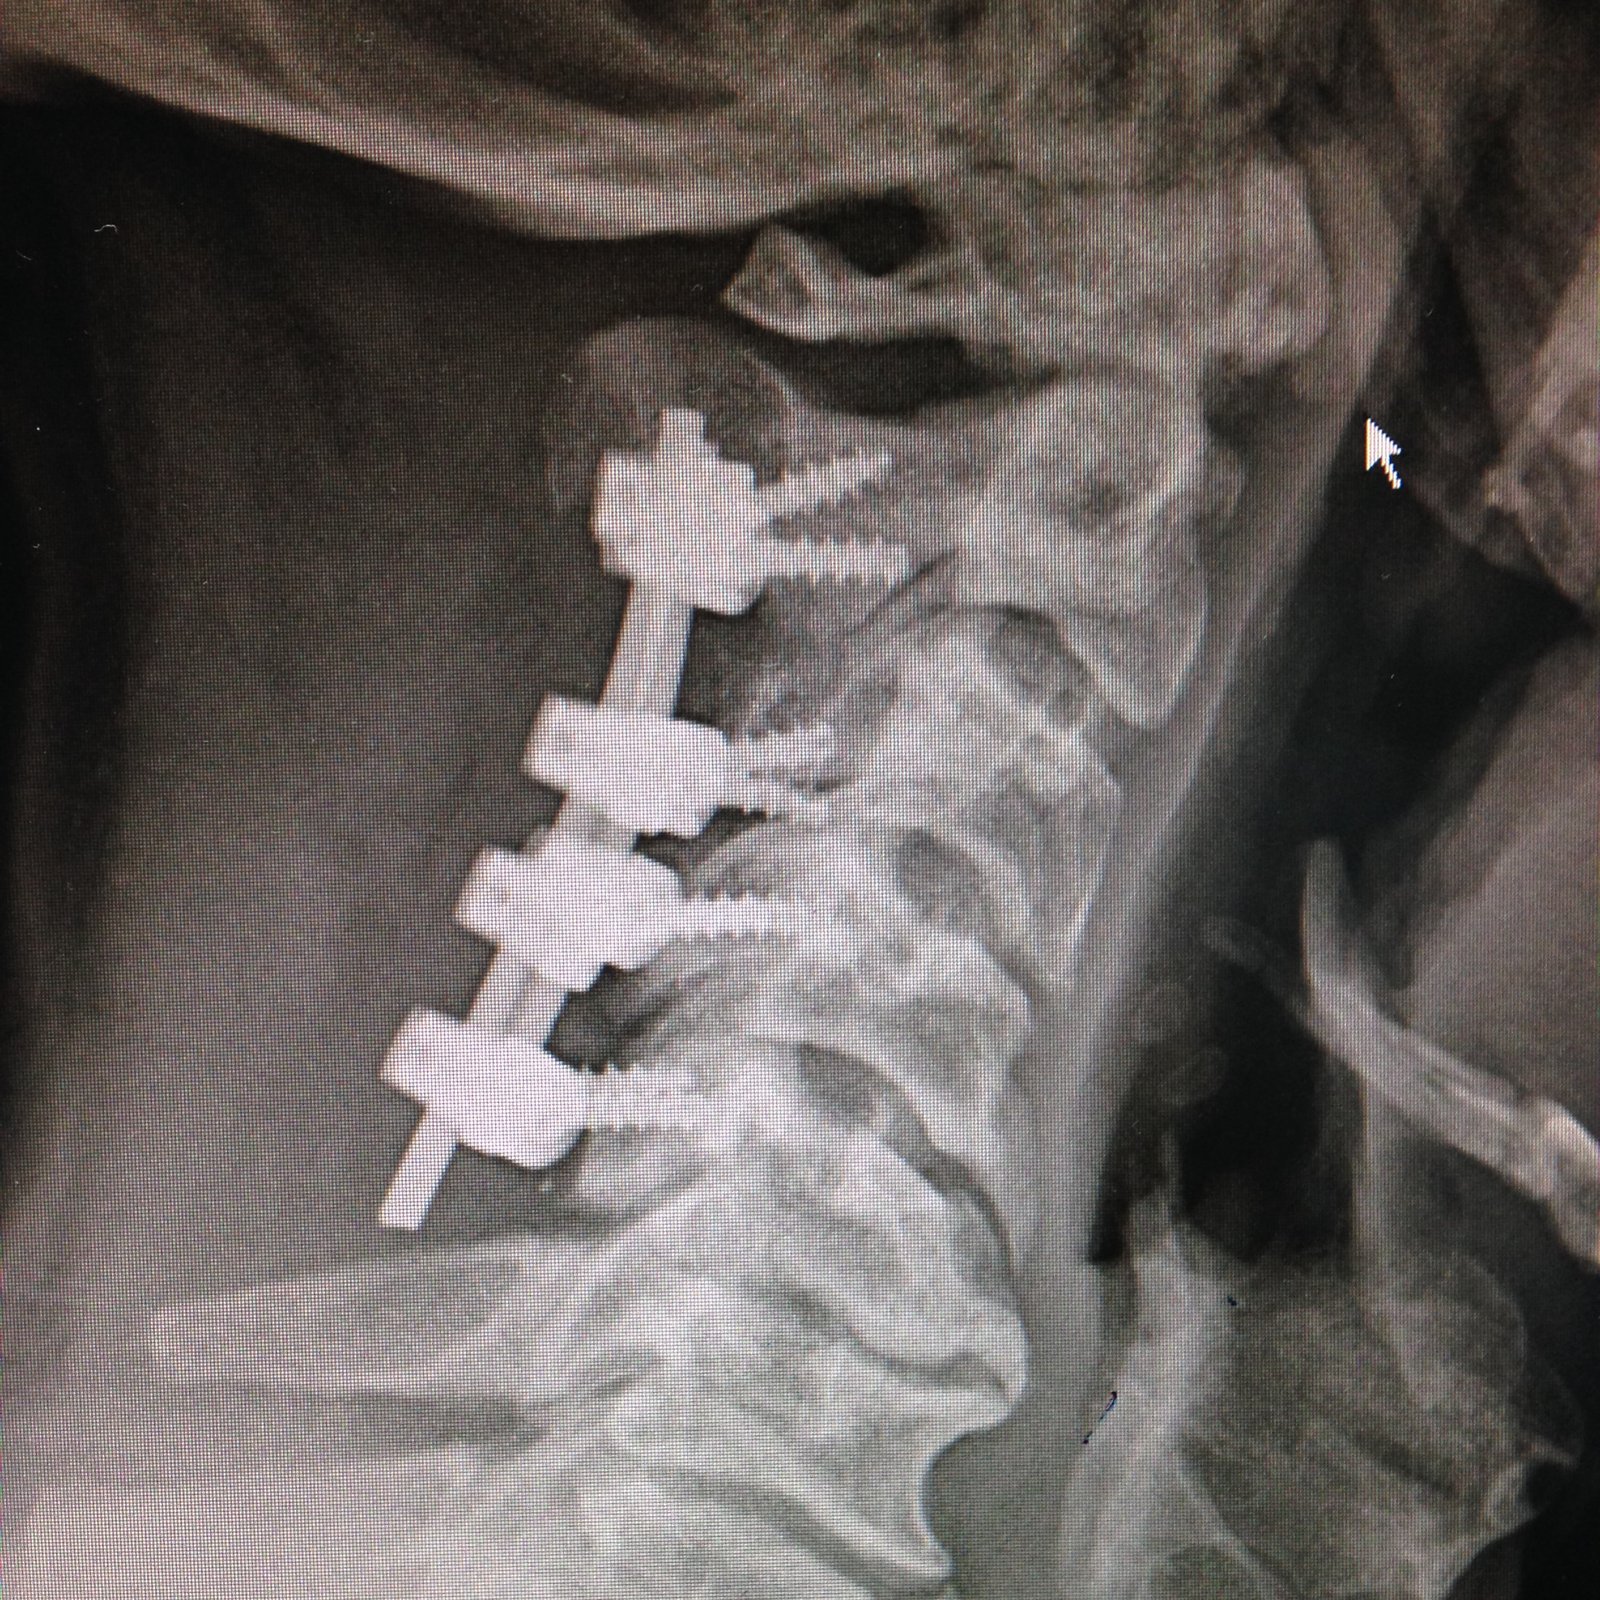

Estimulador de Cordones (SCS)

Tecnología que calma el dolor de forma automática, sin necesidad de cirugía mayor.